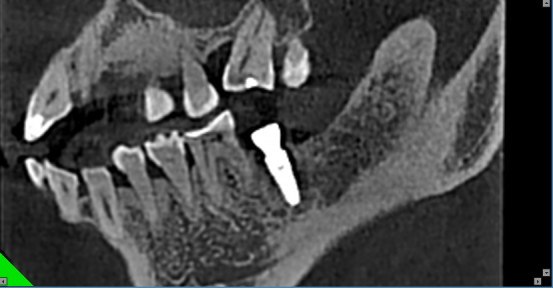

阻生病例2